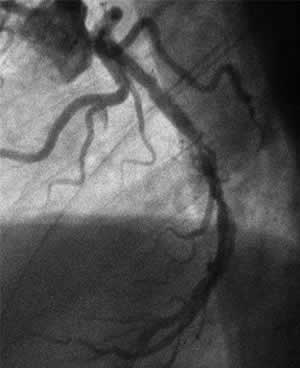

| Diagnosis: OMI (A), TVD

| Final CAG Findings:'01.10.1 LVG: asynergy (A&P), EF: 66% CAG: #2 75%, #6 100%, #12 75%, #13 100% |

J-3 : 3 months follow-up angio